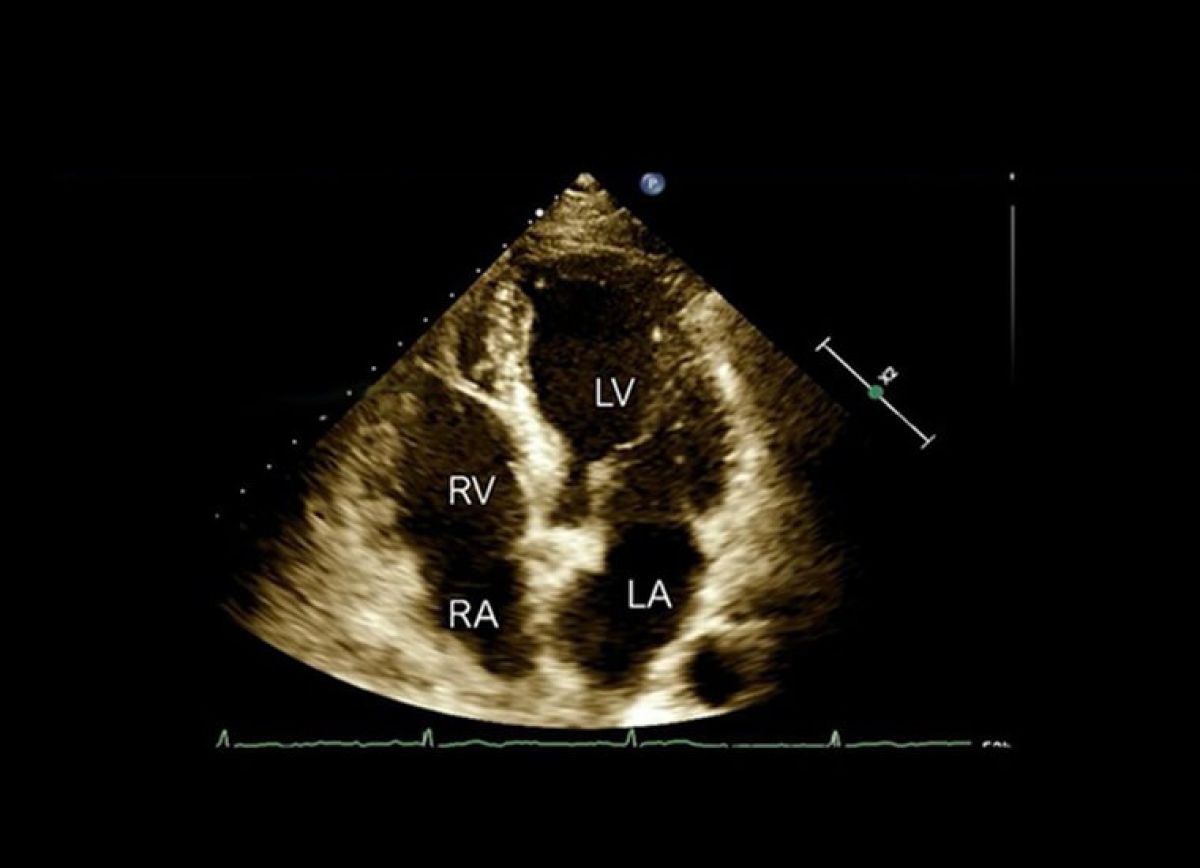

Zatoka wieńcowa, zastawka trójdzielna, prawa komora.

- Przykłady obrazów echokardiografii, które mogą stać się „pułapkami”.

- Na co zwracać uwagę podczas echokardiografii?